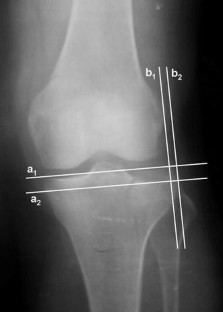

The lateral plateau depression and lateral plateau widening were measured on anteroposterior knee radiographs in 20 patients with Schatzker type II tibial plateau fracture. Meniscal injury was present in 12 patients (three, meniscal tears; nine, peripheral meniscal detachments). The lateral plateau depression and lateral plateau widening measurements were compared between those who had meniscal injury (Group 1) and those who did not (Group 2).

In Group 1, the median lateral plateau depression was 20 mm (IQR: 14–25) and the median lateral plateau widening was 12 mm (IQR: 10–14). In Group 2, the respective values were 10 mm (IQR: 5–17) and 6 mm (IQR: 2–10). There was a statistically significant difference in both parameters when the two groups were compared (p = 0.001).

A plain anteroposterior radiograph depicting a lateral plateau depression ≥14 mm and/or a lateral plateau widening ≥10 mm is associated with a significantly increased risk of meniscal injury in Schatzker type II tibial plateau fractures. These parameters can be used to predict the probable presence of lateral meniscal injury in such patients in routine clinical practice.

Fig. 2